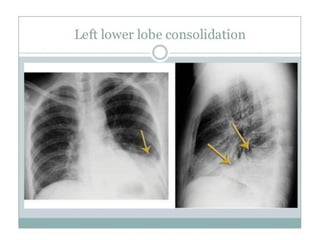

• Lower lobe consolidation

• It is limited by oblique fissure anteriorly

and may obscure diaphragm